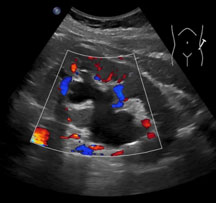

Beim sich anschliessenden Ultraschall der Nieren zeigt sich der Aufstau des Urins in der Niere. Bei unklarem Befund erfolgt noch eine Computertomografie. Mit ihr können weitere Erkrankungen oder sogenannte komplizierende Faktoren (Nierensteine, Eiterhöhlen) ausgeschlossen werden.

![]() |

| Ultraschallbild einer Nierenbeckenabgangsenge | Computertomografie der Nierenbeckenabgangsenge |